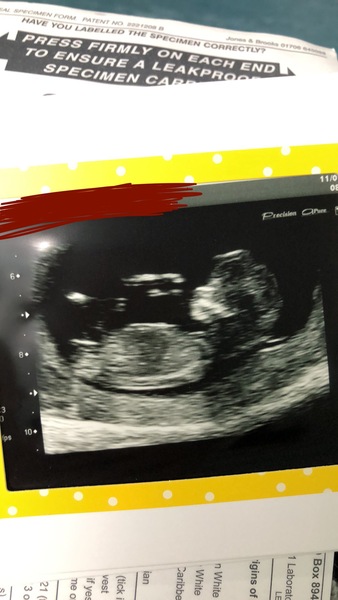

Just had my 12 week scan and wondering if people think my baby is a boy or a girl?

Don’t mind either way- just for a bit of fun guessing:-)xx

That’s a pink one. Congratulations